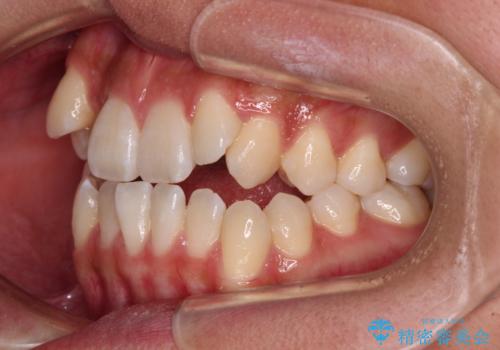

- 前歯の開咬と、上顎前歯の八重歯やデコボコを気にして来院された患者様です。

上顎歯列が狭窄していたため、急速拡大装置により上顎骨を側方に拡大し、その後ワイヤー装置にて矯正治療を行うこととしました。

急速拡大装置で上顎骨を十分に拡大できたことで、非抜歯で八重歯を歯列に納めることができました。